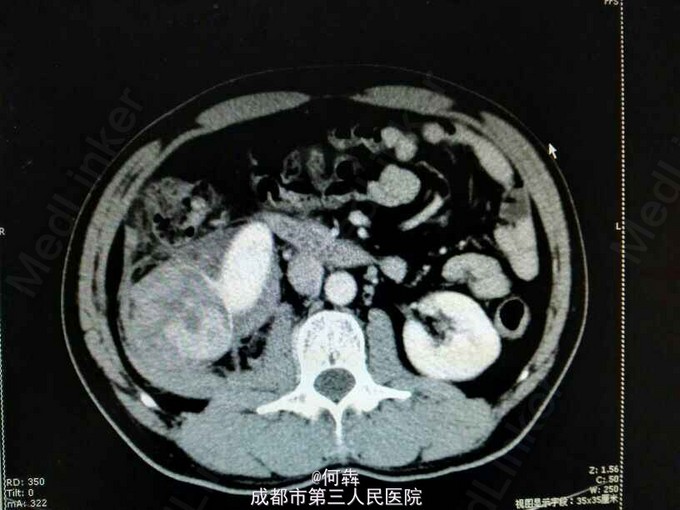

48岁男性,因“突发右腰痛1小时”入院,无血尿、外伤。既往无高血压、糖尿病。

右肾区扣痛阳性,余阴性。

右肾占位伴出血。入院后6天在全麻下行右肾部分切除术。术中冰冻及术后病检见图片

肾上皮样血管平滑肌脂肪瘤(EAML)是肾血管平滑肌脂肪瘤的一种少见亚型。2004版WTO肿瘤分类定义为一种具有恶性潜能的间叶性肿瘤。诊断时则往往与肾细胞癌相混淆。近年较多文献报道,部分EAML易局部复发、侵袭性生长、静脉侵犯、淋巴结或远处转移(以肝和肺转移为主),其预后不佳。